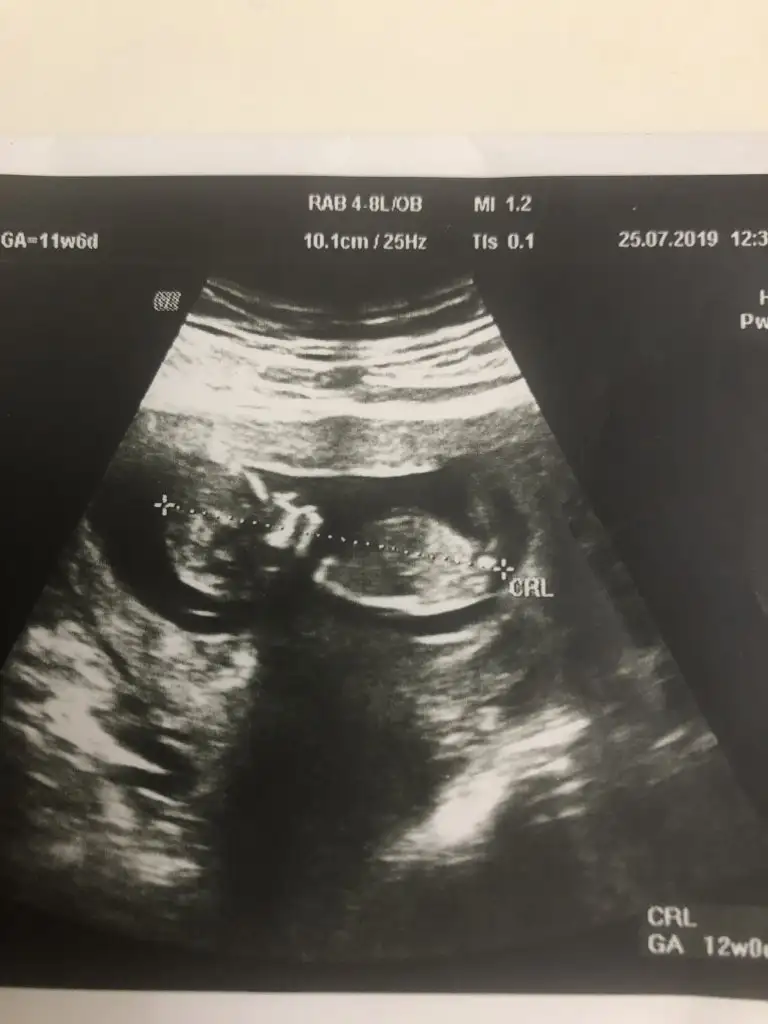

Erkek gibi11 haftalıktahmin alabilirmiyim

Erkek gibi kafa sekline yorumluyorum nub artık olmaz 13 hafta sanırımArkadaşlar daha önce yorum yapmıştınız ama doktor kesin bişey söylemiyor bunada bakabilir misiniz

Evet teşekkür ederimmmErkek gibi kafa sekline yorumluyorum nub artık olmaz 13 hafta sanırım